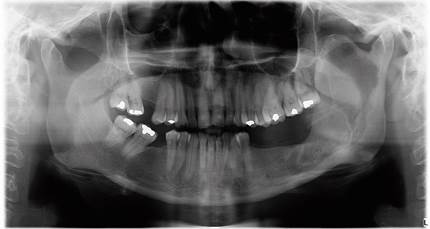

La paciente se mantuvo en control clínico y radiográfico periódico, observándose disminución de la lesión y la aposición ósea mandibular, y la consecuente simetrización facial. Once meses posteriores a la primera intervención quirúrgica, se constató radiográficamente aposición ósea de la lesión radiolúcida del cuerpo y rama mandibular izquierda, límites netos esclerosados y expansión ósea a nivel de la rama mandibular (figura 6), aposición ósea que continúo progresivamente, como se observó en la radiografía panororámica realizada 21 meses postquirúrgica (figura 7).